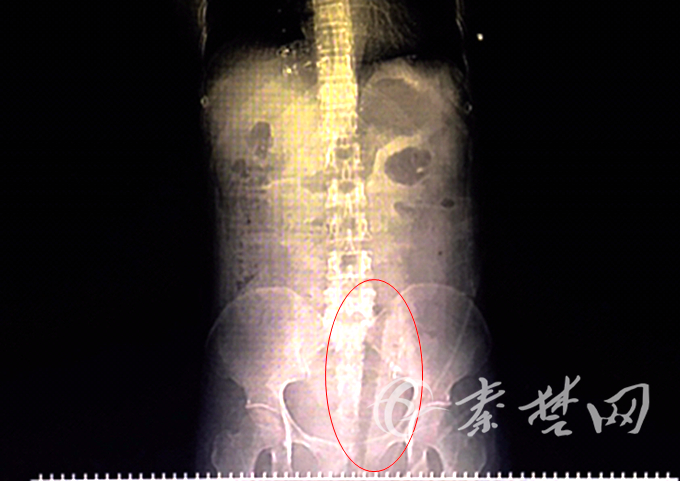

X光下,可见患者体内有异物(红圈所示)。

傍晚时分,陈女士被送达太和医院妇产中心,经紧急检查,断枝从其阴道口插入,并由阴道后壁贯穿而入,由左侧穹窿入盆腹腔。“腹腔镜探查发现,断枝穿透子宫向上贯穿至乙状结肠系膜,顶端插进腹腔十几厘米,到达髂脊水平,断枝末端在阴道外口,外部可见。”妇产中心副主任方彩云告诉记者。

探查清楚断枝所在位置后,由方彩云主刀,刘全、黄润强、孙敏等多科专家共同协作,将断枝完整取出,测量长度为30厘米。